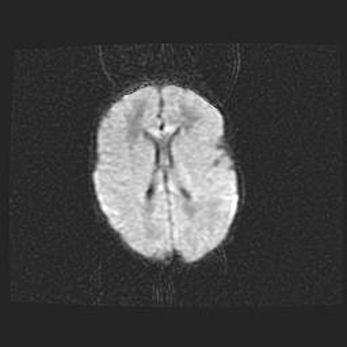

Церебральная ишемия II.

Возраст: 7 дней

Вес: 3350 г

Пол: женский

Окружность головы: 35 см

Срок гестации: 39 недель

Ишемия головного мозга – это состояние, которое развивается в ответ на кислородное голодание вследствие недостаточного мозгового кровообращения. У новорожденных она является следствием дефицита кислорода, что ведет к метаболическим расстройствам различной степени тяжести в тканях головного мозга, в том числе к развитию коагуляционных некрозов и гибели нейронов.